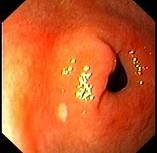

女性,38岁,反复上腹饱胀不适2年,以餐后为甚,伴反酸、嗳气、食欲不振等,体重无明显下降。查体无明显异常。胃镜检查胃窦可见一片状黄色斑块,如下图:该病人最...

问题 女性,38岁,反复上腹饱胀不适2年,以餐后为甚,伴反酸、嗳气、食欲不振等,体重无明显下降。查体无明显异常。胃镜检查胃窦可见一片状黄色斑块,如下图:该病人最可能的诊断是 ( )

选项 A.胃黄斑瘤 B.慢性浅表性胃炎 C.消化性溃疡 D.胃泌素瘤 E.胃癌

答案 A